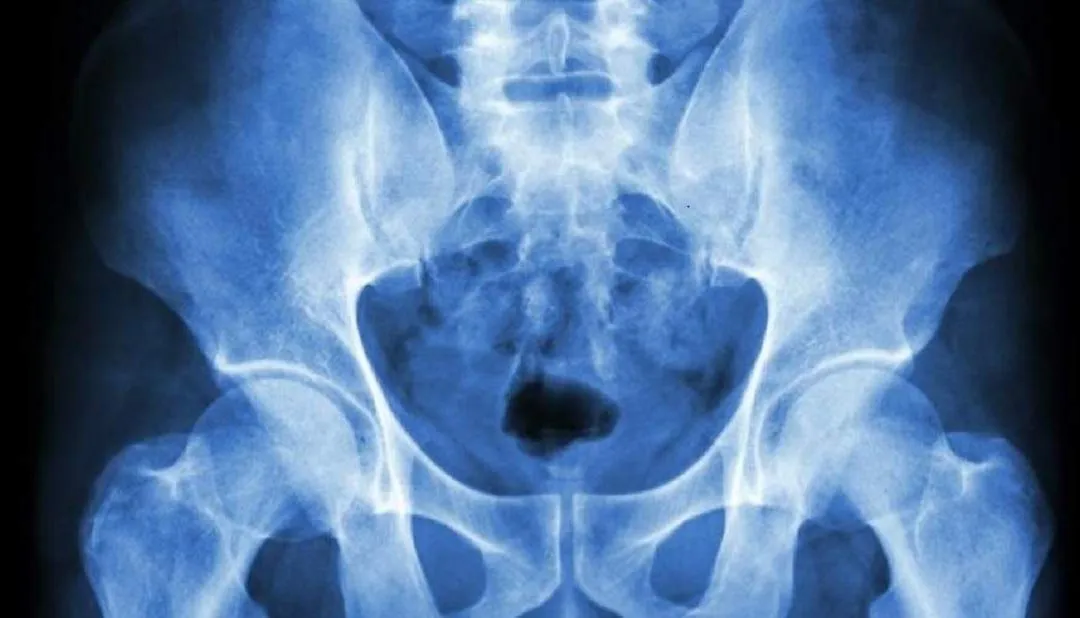

Osteopatía del pubis

La osteopatía puede ser maravillosamente eficaz para aliviar el dolor y las molestias durante el embarazo y el período de recuperación. Quizás la presentación más común de dolor que vemos es el dolor en la sínfisis del pubis, que está relacionado con algo llamado SPD....